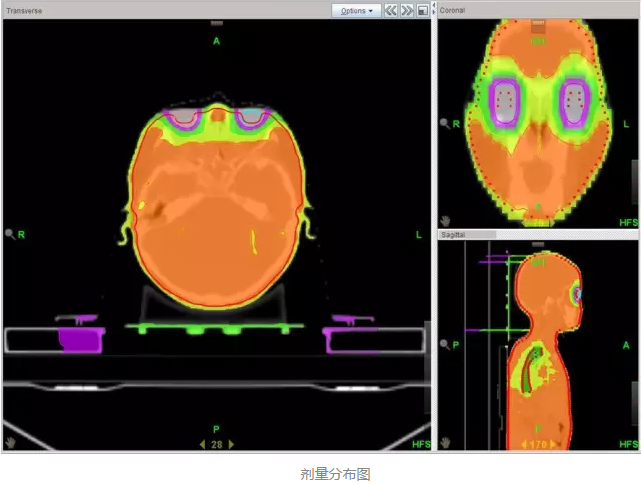

еңЁе®һйӘҢйғ‘еӨ§дёҖйҷ„йҷўйҰ–дҫӢ TBI зҡ„еҺҶзЁӢдёӯ����пјҢж”ҫе°„жІ»з–—йғЁжқҺеӣҪж–Үдё»д»»и®Өзңҹ TBI зҡ„ж•ҙдёӘжүӢиүәжөҒзЁӢ����пјҢйғӯи·ғдҝЎеүҜдё»д»»иҜҰз»Ҷи®Өзңҹе®һйӘҢдёҺеҢ…з®Ў����пјҢеҢ»з”ҹз»„еј ж—ӯдёңеҢ»з”ҹйҳ…иҜ»зӣёе…іж–ҮзҢ®����пјҢ并дәІиҮӘеҲ°ејҖеұ•иҜҘжүӢиүәйўҶе…Ҳзҡ„е№ҝе·һеҶӣеҢәжҖ»еҢ»йҷўж”ҫ疗科еӯҰд№ ����пјҢиҜҘйҷўж”ҫ疗科й»Һйқҷдё»д»»зҡ„ж”ҫз–—еӣўйҳҹз»ҷдәҲдәҶж— з§Ғзҡ„йјҺеҠӣеӨ§дёҫиө„еҠ©���пјӣзү©зҗҶз»„з»„й•ҝ马йҳіе…үеҗ‘еҜјзү©зҗҶз»„е…ЁдҪ“иҒҢе‘ҳиө·еҠІеҚҸи°ғ����пјҢзҺӢжө·жҙӢзү©зҗҶеёҲдҪҝз”Ёе‘ЁеӨ©дј‘жҒҜзҡ„ж—¶й—ҙдёҫиЎҢиҙЁйҮҸжҺ§еҲ¶жқҘзЎ®���пјӣйўҠе’§зҳҹзІ•зі»йӮЈеҜ°���пјӣжүӢиүәз»„з»„й•ҝжӣ№дҝҠеҚҺеҗ‘еҜјжүӢиүәз»„е…ЁдҪ“жҲҗе‘ҳж”»еқҡе…Ӣйҡҫ����пјҢжңҖз»ҲеңЁеҗ„дёӘйғЁеҲҶзҡ„й…ҚеҗҲиө·еҠІдёӢ����пјҢ2016 е№ҙ 5 жңҲ 16 ж—Ҙйғ‘е·һеӨ§еӯҰ第дёҖйҡ¶еұһеҢ»йҷўйҰ–дҫӢ TBI жІ»з–—е®ҢжҲҗ����пјҢз”ұдәҺж”ҫе°„жІ»з–—йғЁдҪҝз”Ё TOMO HD еҠ йҖҹеҷЁе®һйӘҢзҡ„ TBI ����пјҢеүӮйҮҸжј«иЎҚеҚҒеҲҶе®Ңе–„пјҲеҰӮдёӢеӣҫжүҖзӨәпјү����пјҢзұ»дјјй•ҢеҲ»����пјҢд»ҘжҳҜеҸҲиў«з§°дёәгҖҢй•ҢеҲ»ејҸе…Ёиә«ж”ҫз–—гҖҚ����гҖӮ